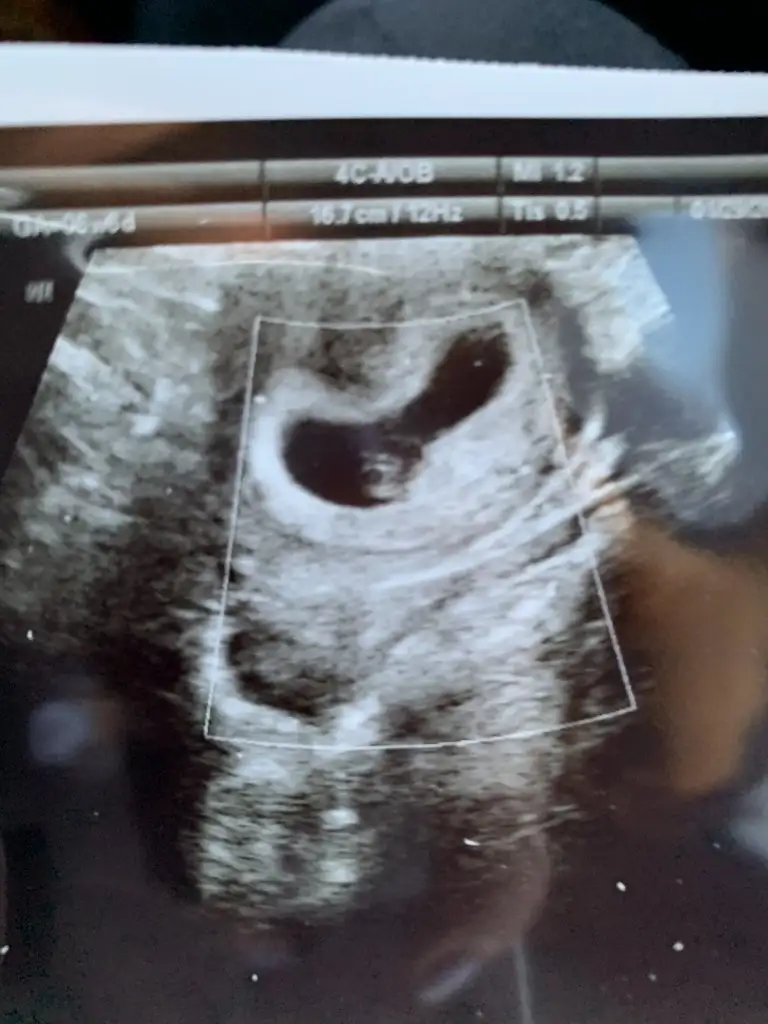

Eki Görüntüle 2771827 Kızlar sata göre 5+4 ama sizde daha geriden mi geliyor acaba ? Kese oluşmuş dedi hcg 4.000 di dün ultrason bugüne ait

Benim de ilk muayenemde kesem böyle küçüktü uygulamada 5 + gösteriyordu ama doktor 4.5 haftalık demişti biraz kafama da takmıştım niye küçük niye geride diye ama 6+4 de uygulamada 6+3 gösteriyordu kalp atışını duydum için ferah olsun sağlıklı devam etsin inşallah gebeliğin

Bende 6+2yim kesede bebek de kap arısı sa görüldü. Cınsiyet tahmini yapabilen varmı bır teori vatdı😃bır arkadas teoriye göre bakıyordu

Kızlar karın ultrasonunda bebişim ❤️ Cinsiyet tahmini rica edebilir miyim🥰